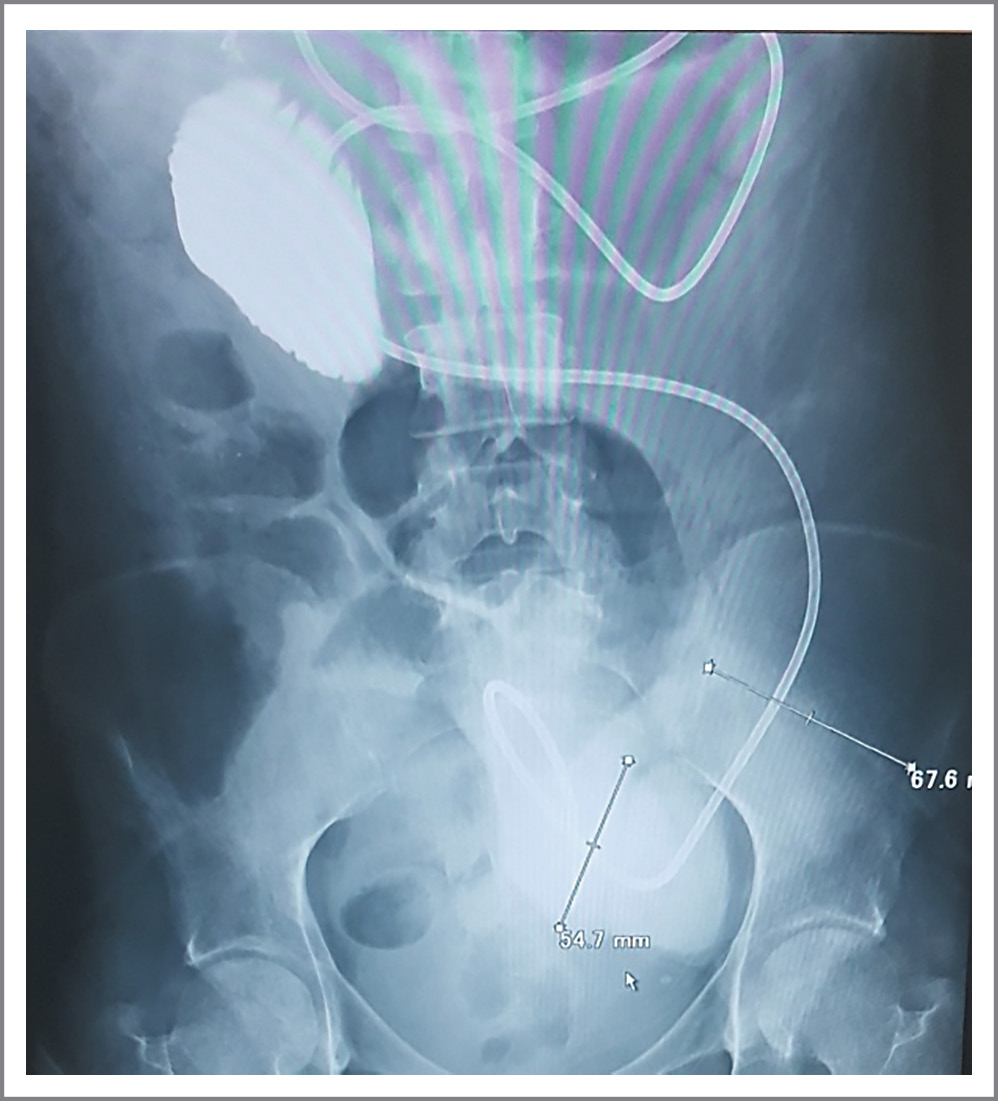

На обзорных рентгенограммах органов брюшной полости в положении полулежа петли ТК расширены до 66,3 мм; скопление газа и жидкости в подвздошной и восходящем отделе ободочной кишки (рис. 1).

Рис. 1. Рентгенограмма брюшной полости больной А.

Fig. 1. X-ray of the abdominal cavity of patient A.